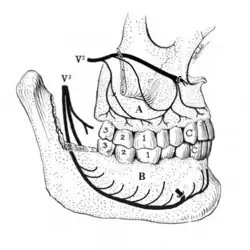

Apical periodontitis is acute or chronic inflammation around the apex of a tooth caused by an immune response to bacteria within an infected pulp.[20] It does not occur because of pulp necrosis, meaning that a tooth that tests as if it's alive (vital) may cause apical periodontitis, and a pulp which has become non-vital due to a sterile, non-infectious processes (such as trauma) may not cause any apical periodontitis.[10]: 225 Bacterial cytotoxins reach the region around the roots of the tooth via the apical foramina and lateral canals, causing vasodilation, sensitization of nerves, osteolysis (bone resorption) and potentially abscess or cyst formation.[10]: 228

The periodontal ligament becomes inflamed and there may be pain when biting or tapping on the tooth. On an X-ray, bone resorption appears as a radiolucent area around the end of the root, although this does not manifest immediately.[10]: 228 Acute apical periodontitis is characterized by well-localized, spontaneous, persistent, moderate to severe pain.[6]: 125–135 The alveolar process may be tender to palpation over the roots. The tooth may be raised in the socket and feel more prominent than the adjacent teeth.[6]: 125–135